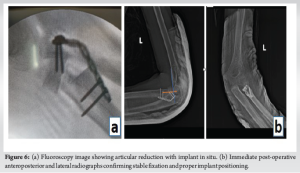

The radial head osteotomy with resurfacing was done (Fig. 5b) as planned pre-emptively on our 3D model, and fixation and alignment were done and held in place using AO 5-holed radial head ring plate (Fig. 6a). Fluoroscopy was used to confirm appropriate articular reduction and position of implants in situ. Intraoperatively, full range of motion was executed passively on the table. The elbow joint appeared to be stable throughout its range of motion. The wound was closed in layers, and sterile dressing was done. Post-operative X-rays were taken (Fig. 6b and c). The patient was placed in an arm pouch. Dressing was done once every 3 days.